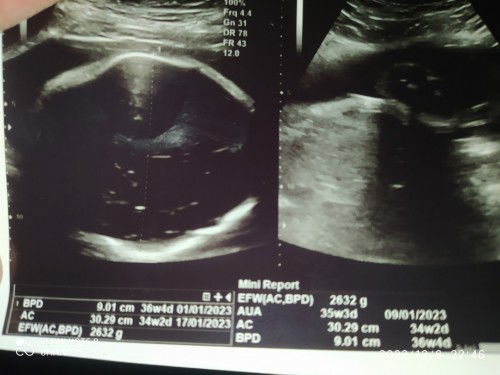

akurat mana hitungan hpl kalender atau hpl USG??

#seriusnanya #bantusharing #ingintahu tadi sya hbis usg bun, dan Alhamdulillah debayx sehat, tpi umur janin tdk sesuai ukuran janin, dokterx tanya berkli" hpht saya, tkut slh hitung ktnya, pdhal sya yakin loh itu sdh bener hphtx, dan klok di klender hpl sya 3 feb 2023, sdngkan tadi brubah bln januari, ini yg akurat yg mna yaaa bunn...... jadi bingung sndri